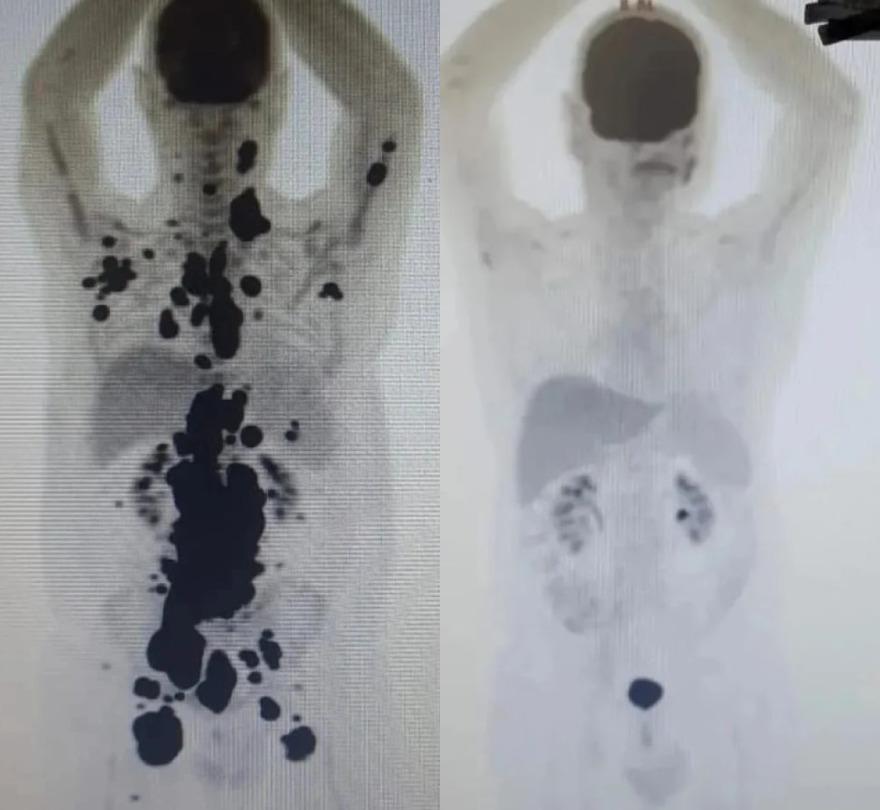

O PET scan realizado antes do tratamento mostra o câncer espalhado pelo corpo. No exame seguinte, as células tumorais já haviam desaparecido – as manchas pretas permanecem nos rins e cérebro devido ao contraste utilizado.